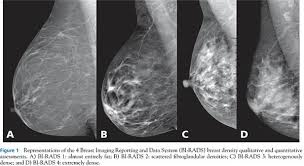

To determine whether that lump is benign, your doctor will likely order a mammogram and breast ultrasound. Breast mri images are combined, using a computer, to create detailed pictures. People should become familiar with the typical look and feel of their. Not all women have calcifications in their breasts—but most do. Generally speaking, the denser the tissue, the whiter it appears.

Generally speaking, the denser the tissue, the whiter it appears. These deposits show up as tiny white spots on a mammogram, and there may be only one or two, or too many to count, says jay baker, md, a breast imaging specialist at the duke cancer center.most people assume that what doctors are looking for on a mammogram are lumps, dr. Not all women have calcifications in their breasts—but most do. A mammogram image has a black background and shows the breast in variations of gray and white. Rate of dcis discovery is increasing, due to screening mammograms. If microcalcifications are found on your mammogram, the radiologist will do the following to help determine what if anything needs to be done: What does breast cancer look like? If you have calcifications, they'll show up as white spots. Generally, whiter mammogram images indicate denser breasts. This can make it harder for your radiologist to spot signs of breast cancer, since dense tissue and tumors both look white in mammogram images. However, a mammogram is not perfect and it is difficult to detect abnormalities in a person with dense breasts. People should become familiar with the typical look and feel of their. It's common to have dense breasts.

The person having the mammogram will place their breast between … However, cancer can also be seen as white, making it a bit obscure in women with extremely dense breasts. They can vary greatly from painful, hard, and immobile to soft, painless, and easily moveable. Specialist doctors (radiologists) trained to interpret mammograms can identify any abnormal areas, masses or calcium. So, an ultrasound is typically a 'second look' type of application.